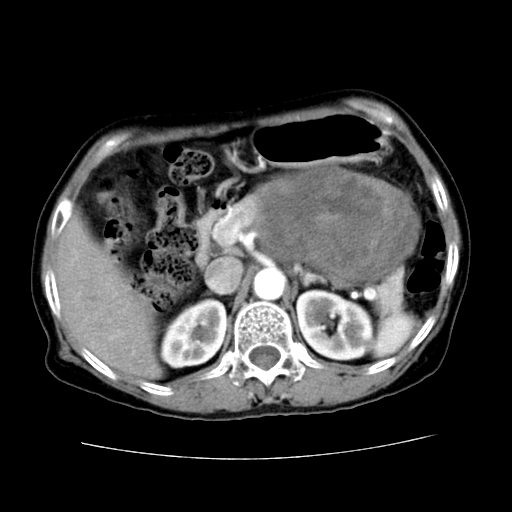

女性,72岁。

主诉中上腹部疼痛不适1年余。

胰腺尾部不规则巨大略低密度肿块,界限清楚,内密度不均,增强动脉期不均匀强化,门脉期明显退减并低于胰腺密度,肿瘤包埋于脾血管。多考虑;来源于胰腺尾部的“胰腺癌”。

考虑胰体尾部囊腺癌可能性大。肝右叶可疑转移.

1、这个病例确实有点难。影像主要显示胰腺体尾部占位,我们当初也是诊断胰体尾部囊腺癌可能性大,而且读片会上也很多人这么诊断的。

2、手术所见:打开腹腔发现胃与胰腺体尾部可见肿块,大小约10×8×11cm,质硬,不可推动,周围血供丰富。术中诊断:胃肿瘤侵及胰腺体尾部。

1)、胃小弯侧胃肠间质瘤(考虑恶性),瘤体大小13.5×7×6.5cm,上下切缘阴性。

2)、胃小弯1只、幽门下2只淋巴结慢性炎。免疫组化:cd117(+)、cd34(+)、sma(+)、desmin(-)、s-100(-)、ki-67<10%(+).

4、这个肿瘤太大了,而且密度不均性强化,从这点我们应该不能单纯诊断胰腺癌,而应想到目前流行的胃肠道间质瘤。这个肿瘤主要发生于胃壁浆膜层,所以显示与胃壁关系不是很紧密,故而大多认为是胰腺癌。

谢谢反馈结果,如楼主分析,本病例主要肿块与胃壁见有分界,而与胰腺分界不清,故而首先考虑胰腺肿瘤。